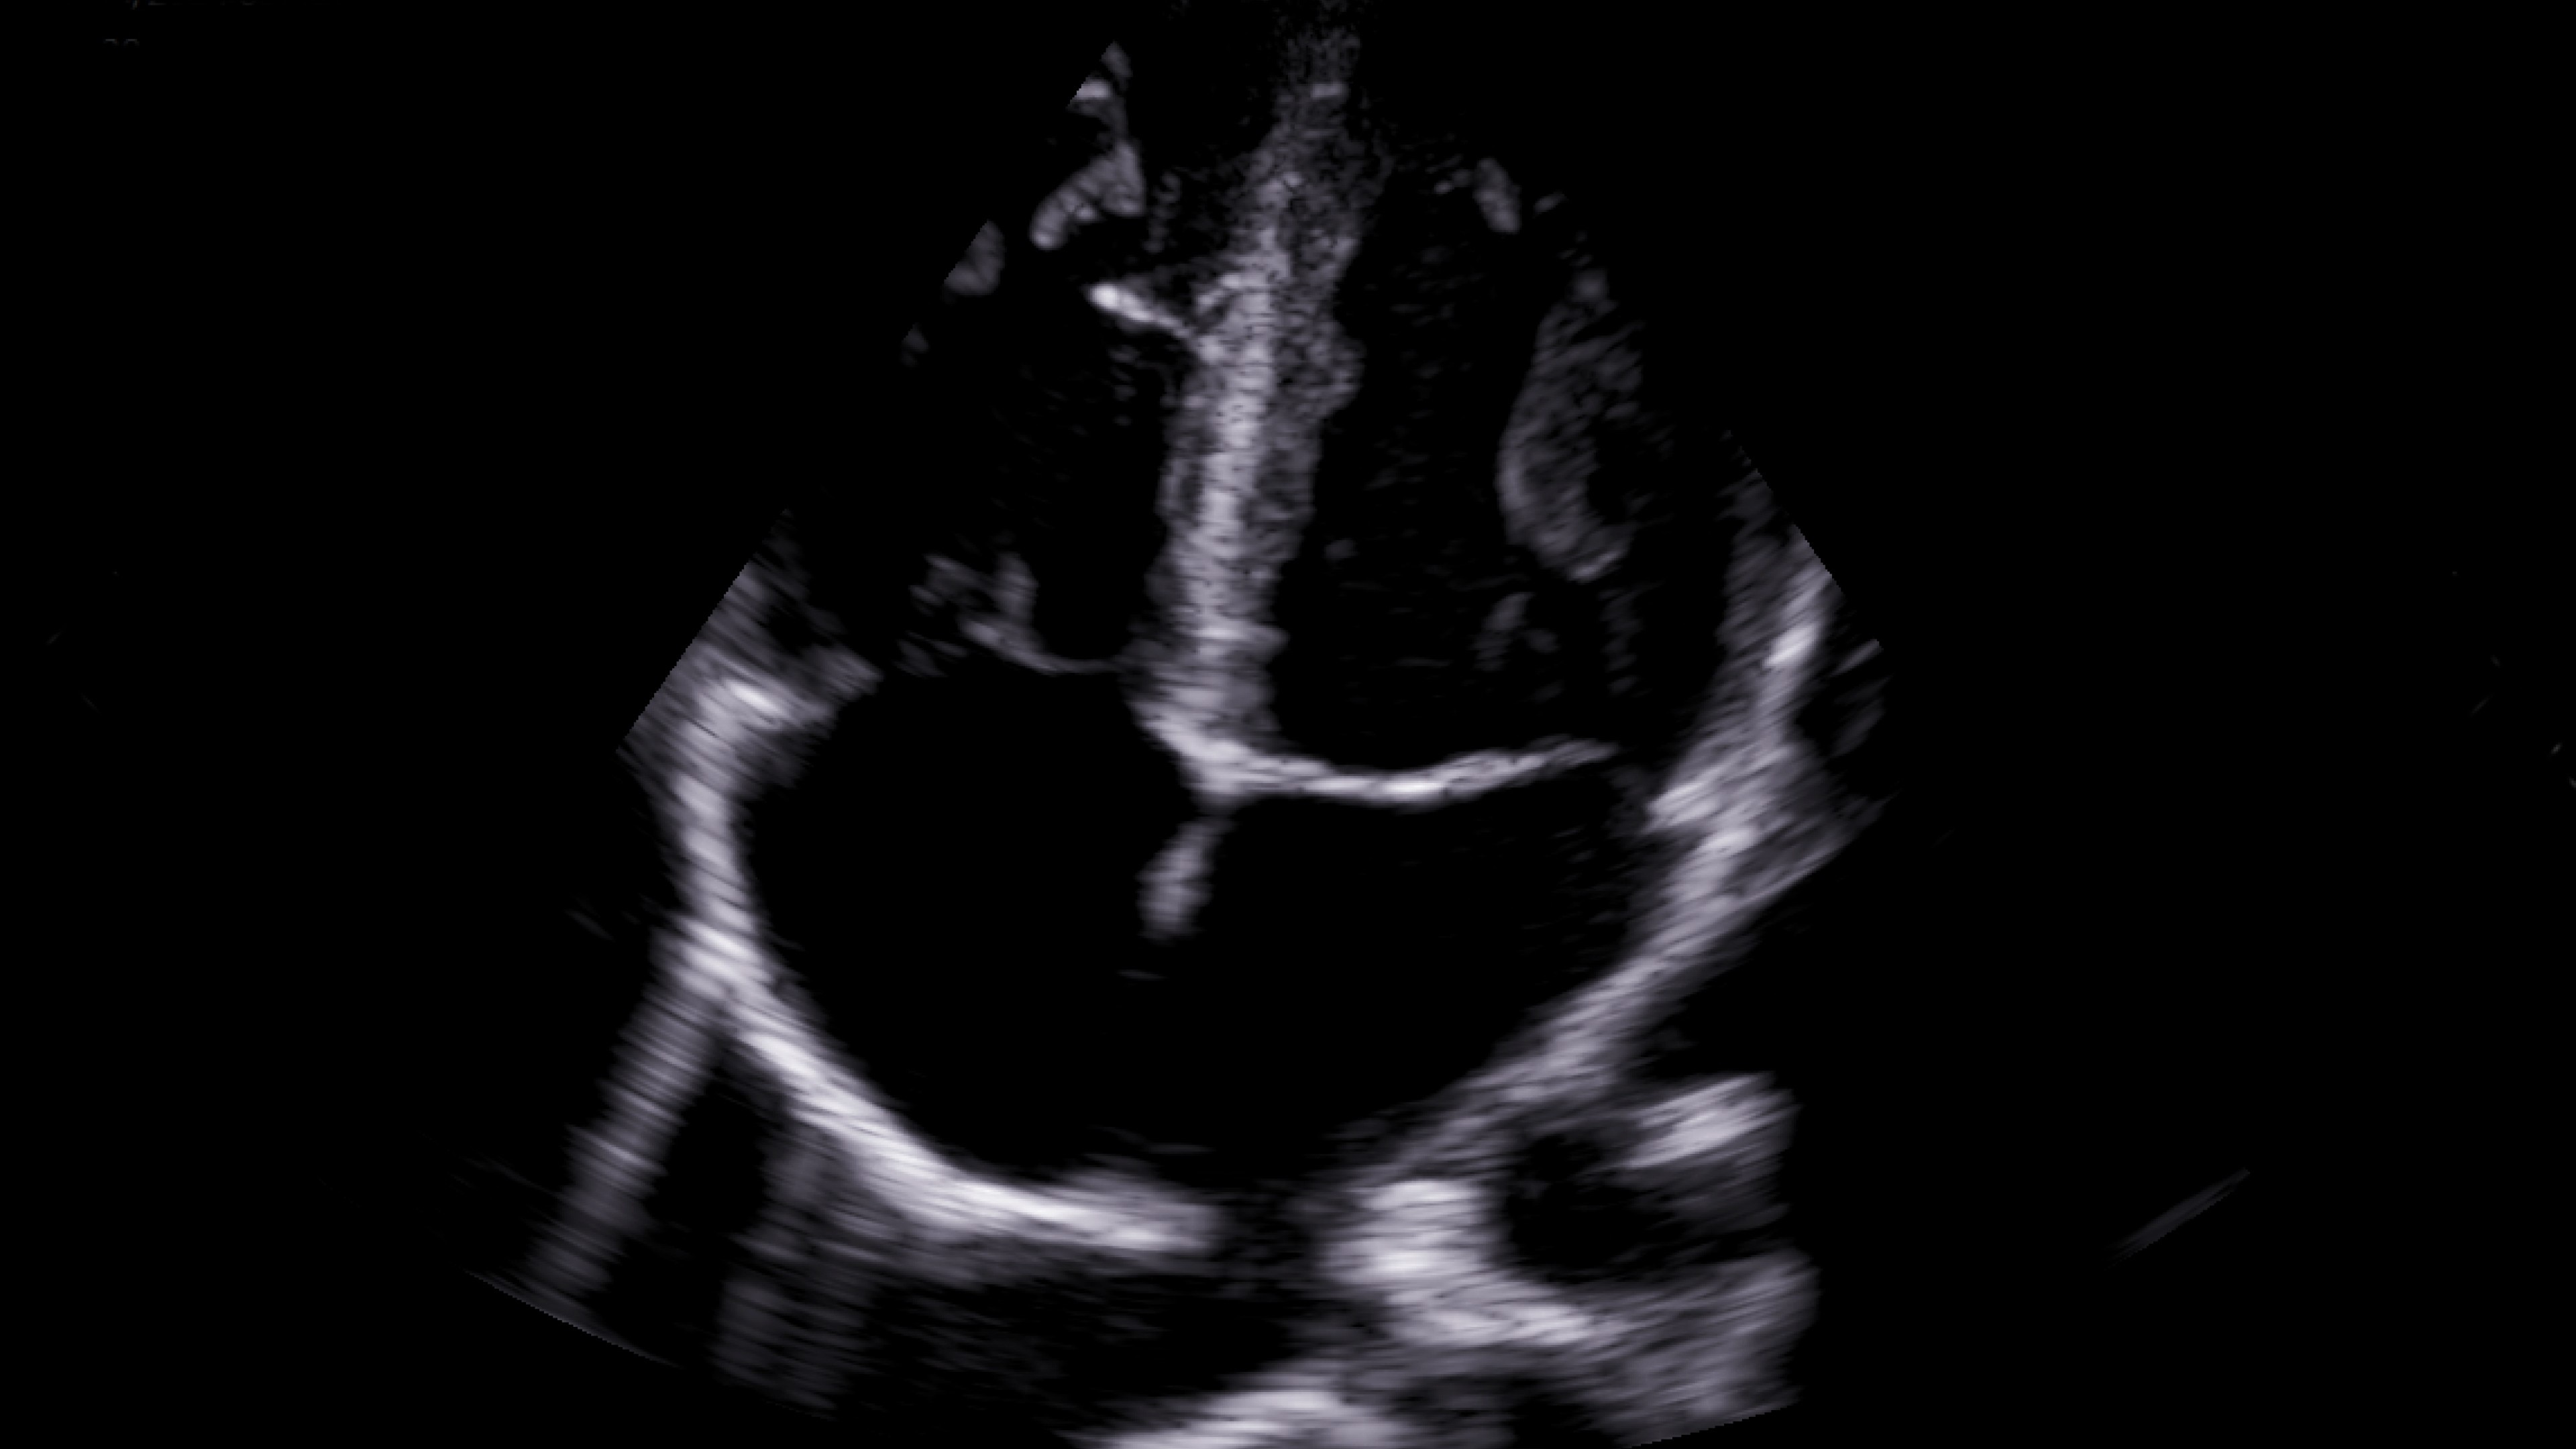

Emergency medicine

Enables assessments for a variety of anatomy all with a single device. Supports deep and shallow scanning with seamless data connectivity.